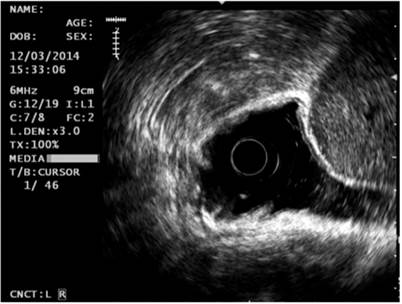

Based on the endoscopic findings, it was decided to extend the study through gastric endoscopic ultrasonography. It showed an elevated 20 mm hypoechoic lesion in the corpus that infiltrated into the mucosa and partially into the submucosa. In the antrum, a 60 mm in diameter subepithelial lesion with cystic spaces inside was found in the muscularis propria (Figure 2). No perilesional or celiac trunk adenopathy was found, and a diagnosis of early GC and GIST in the fourth layer was made. The biopsy taken from the lesion in the gastric corpus confirmed that it was a moderately differentiated gastric adenocarcinoma. A contrasted abdominal CT scan showed no metastasis from the GIST.